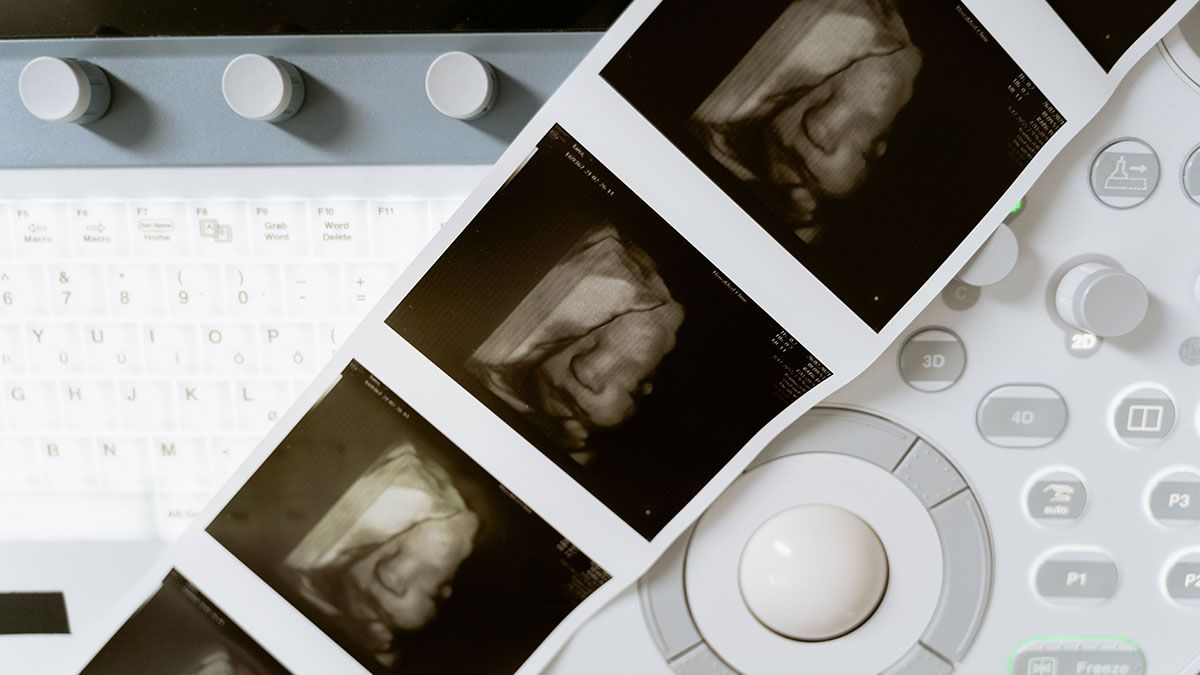

Hello Mom se vincula con los sistemas de ultrasonido Samsung Medison para transferir imágenes de ultrasonido del feto y registros de crecimiento directamente al teléfono móvil de la madre.

Con esta nueva aplicación, los padres podrán hacer un seguimiento de la gestación desde el inicio, tener un recuerdo del desarrollo del bebé dentro del útero y compartir, con quién deseen, vídeos o fotos de la gestación.